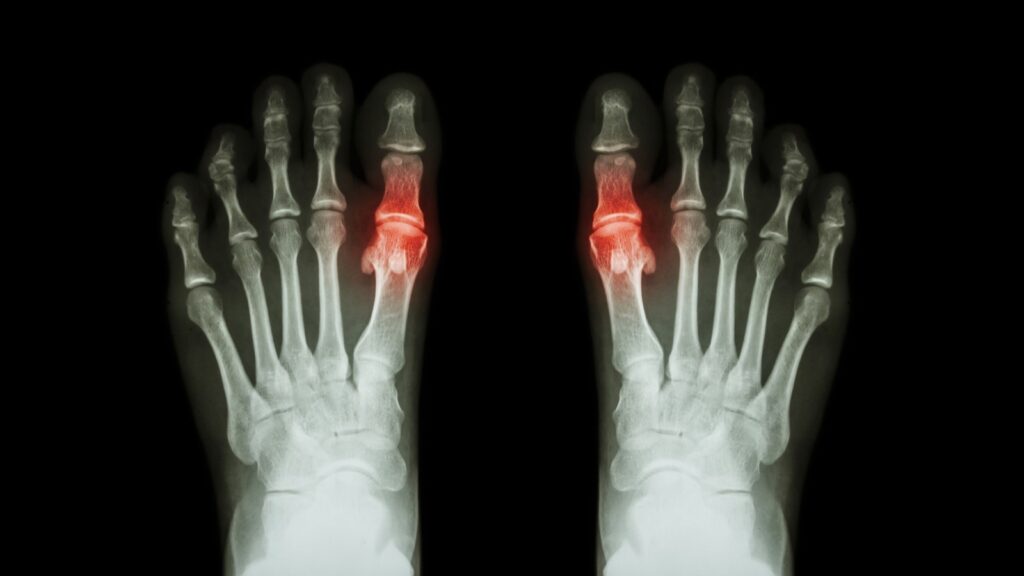

Rheumatoid arthritis is actually a form of chronic inflammatory autoimmune disease, meaning that the immune system actually attacks the tissue that lines the joints. This inflammation and attack from the immune system causes damage to the cartilage and bones within the joints as well as the tissue which is what leads to the pain and swelling.

Osteoarthritis is the most commonly seen form of arthritis for those who struggle with it. It’s a degenerative condition that causes the cartilage found within the joints to break down, and without the cartilage to cushion them it causes the bones to rub together, leading to pain and inflammation in the affected area.

Osteoarthritis commonly affects the joints within the big toe, but it can also affect the rest of the foot and ankle.